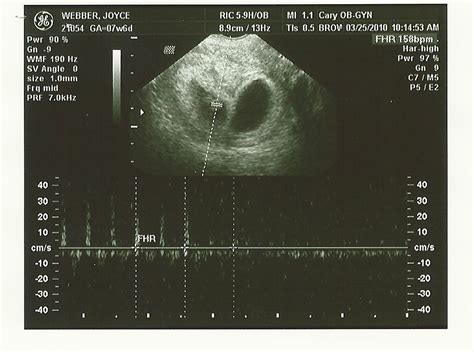

8 week ultrasound - Martin Blog